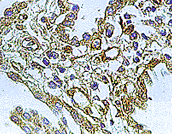

WB/IH/IP技術